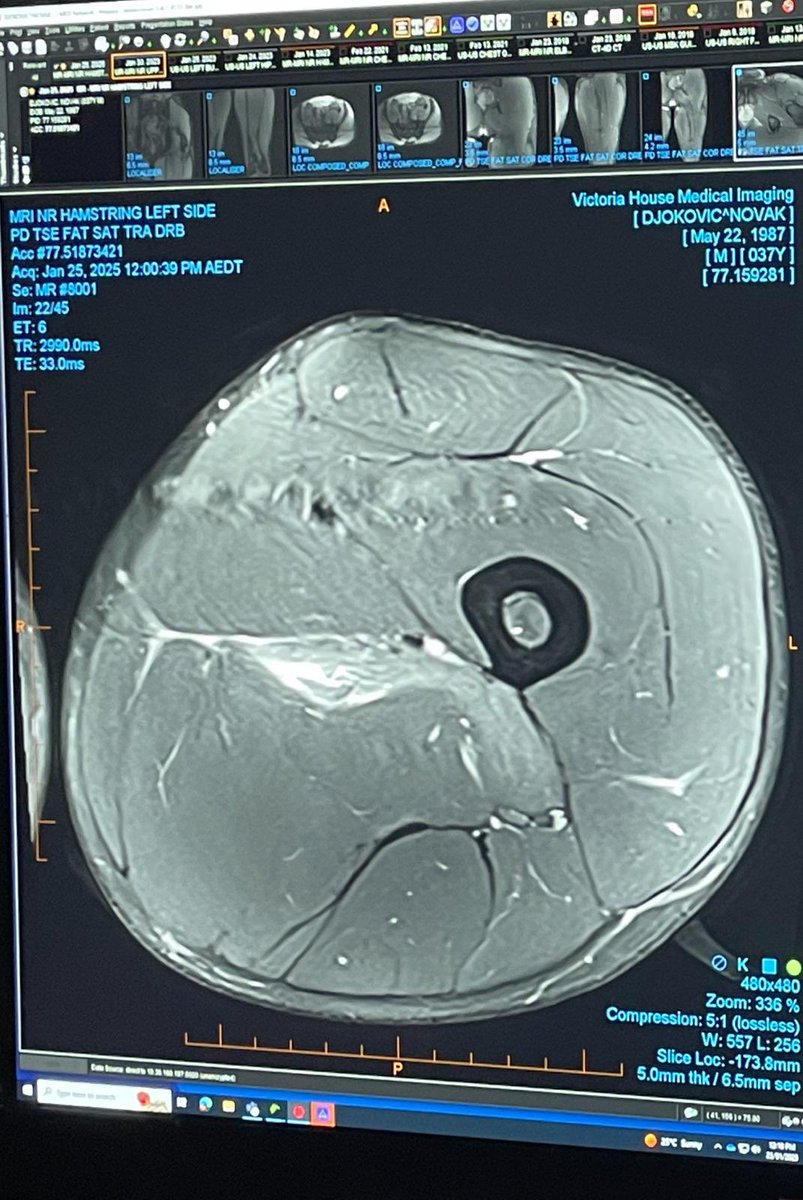

Hal serupa juga dialami petenis legend asal Serbia, Novak Djokovic. Djokovic telah dipanggil badan otoritas tenis Australia karena mengunggah hasil pemindaian cedera lututnya pada saat dunia tenis merayakan kemenangan grand slam perdana Madison Keys.

Novak Djokovic share foto hasil scane lututnya robek (Foto: Istimewa)

Novak Djokovic dikritik karena waktu pengungkapan cedera

Dan sementara Sabalenka akan menunggu untuk mengetahui hukumannya, para penggemar telah mengkritik Djokovic karena waktu tanggapannya terhadap kritik. Sementara dunia tenis merayakan kemenangan grand slam Keys yang epik, banyak yang merasa Djokovic salah waktu dalam mengkritik dan mengalihkan perhatian dari juara putri tersebut. Djokovic dicemooh secara tidak adil di luar lapangan selama semifinal setelah ia mengundurkan diri karena cedera setelah satu set melawan Alexander Zverev.

Djokovic mengalami cedera hamstring dalam pertandingan perempat final melawan Carlos Alcaraz saat ia berjuang keras untuk meraih kemenangan dalam empat set. Ada keraguan mengenai apakah Djokovic akan mampu bermain melawan Zverev di semifinal, dengan banyak yang merasa bahwa petenis Serbia itu tidak cedera seperti yang terlihat pada awalnya. Hal ini karena ia mampu menyelesaikan pertandingan yang menegangkan melawan Alcaraz dan tampak bergerak lebih baik.

John McEnroe dan Jim Courier sepakat bahwa Djokovic bergerak cukup baik hingga ia tiba-tiba mundur. Beberapa penggemar di Rod Laver Arena tanpa basa-basi mencemooh Djokovic di luar lapangan, yang memicu kegemparan. Dan sebagai balasan atas kritiknya, Djokovic mengunggah hasil pemindaian yang memperlihatkan otot paha belakangnya yang robek di media sosial pada Minggu pagi.

Meskipun hasil pemindaian itu memperlihatkan bahwa ia mengalami cedera serius di semifinal, unggahan itu tidak diterima dengan baik oleh semua orang. Beberapa orang merasa Djokovic seharusnya menunda mengunggah hasil pemindaiannya agar ia tidak mengalihkan perhatian dari Keys beberapa jam setelah kemenangannya.

Postingan Djokovic menjadi berita yang lebih besar pada Minggu pagi daripada kemenangan Keys, dengan banyak media memberitakan hasil pemindaiannya lebih tinggi daripada hasil final putri. Namun, yang lain merasa Djokovic pantas membungkam para pengkritiknya karena telah diperlakukan tidak adil saat mundur karena cedera.

Sebuah jajak pendapat pembaca Yahoo Sport Australia telah mengungkapkan sekitar 30 persen percaya bahwa unggahan Djokovic mengalihkan perhatian dari Keys. Namun, lebih sedikit pembaca yang menganggap Djokovic berhak mengunggah hasil pemindaian, dengan mayoritas (45 persen) menyatakan bahwa ia tidak perlu mengunggahnya sama sekali - terlepas dari waktunya.

Terlepas dari itu, Djokovic mengucapkan selamat kepada Keys melalui unggahan di media sosial dan juga berbagi pemikiran untuk Sabalenka setelah nyaris kalah. Jannik Sinner kemudian mengalahkan Zverev di final setelah tampil memukau untuk memenangkan gelar Australia Terbuka keduanya berturut-turut.(*/saf/yahoo.news)